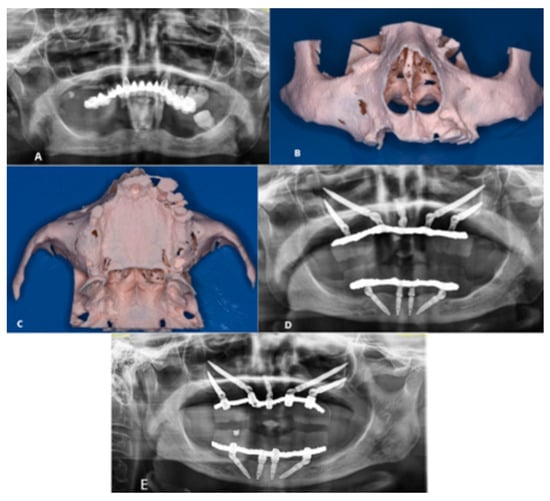

The patient reported no post-operative issues, which was substantiated by the findings at the 6-month follow-up (Figure 2).

Figure 2. (A) Pre-operative OPT; (B) Anterior view of the SLA model; (C) Inferior view of the SLA model; (D) Post-operative OPT; (E) 6-Month Follow-Up.